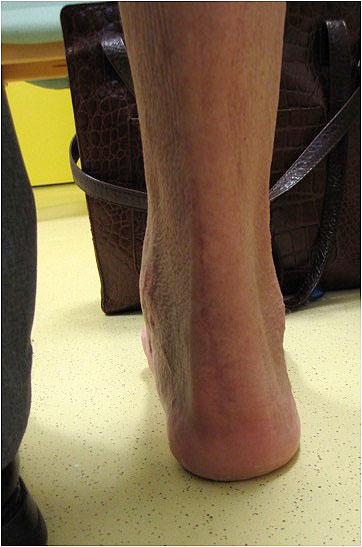

Chronische Achillessehnenrupturen unterscheiden sich dagegen häufig in der Anamnese und dem klinischen Bild. Das Unfallereignis liegt in der Regel lange zurück und war – sofern die Patienten sich noch daran erinnern können – eher ein Bagatelltrauma. Bei Patienten mit systemischen Erkrankungen (Diabetes mellitus, Hyperurikämie, Kortisondauertherapie, Antibiotikagabe) ist ein Trauma oftmals nicht der Auslöser für die Ruptur. Hier handelt es sich vielmehr um einen schleichenden Prozess mit rezidivierenden Mikrotraumata und resultierenden Patialrupturen. Subjektiv eingeschränkt sind die Patienten vor allem bei Alltagsbewegungen wie Treppen steigen oder das Laufen auf ansteigenden Rampen. Auffällig häufig stellen sich bei uns Patienten vor, die bei Wanderungen im Gebirge eine Kraftlosigkeit im betroffenen Bein bemerken. Auch beschreiben sie einen diffusen Fersenschmerz. Eine Dehiszenz lässt sich durch die narbige Überbrückung in der Regel nicht palpieren. Eine Ausnahme bilden hier veraltete knöcherne Ausrisse, die eine typische Konturierung der Fersenregion bedingen (Abbildung).

Abbildung 3a

Abbildung 3b

Der Thompson- Test ist bei diesen Patienten nicht regelhaft positiv (Video 2). Ausschlaggebend ist die Seitendifferenz des Befundes. Gleiches gilt für den Matles- Test. Der Einbeinzehenspitzenstand kann von den Betroffenen meist auch nicht ausgeführt werden. Wenn doch, dann ist die seitendifferente Ausprägung ein wichtiges diagnostisches Mittel (Video 3).